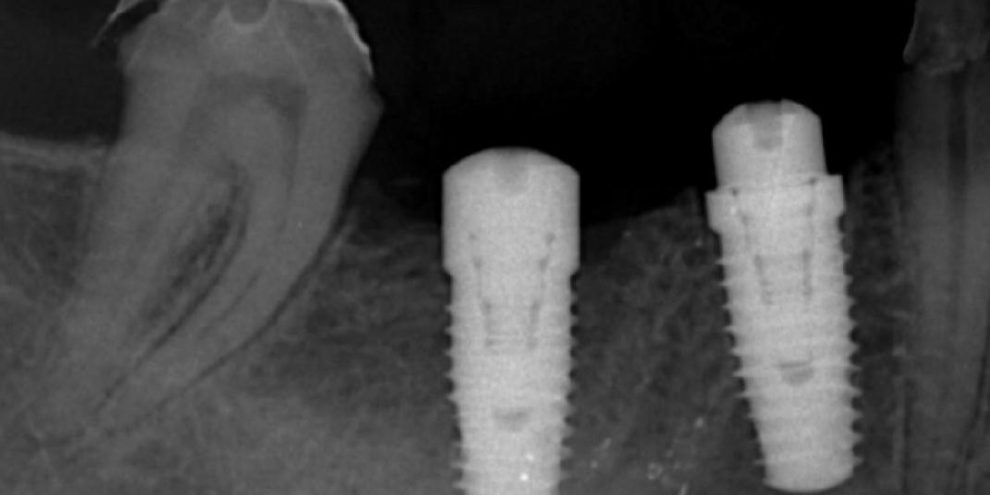

รากเทียมโดยทีมอาจารย์ มข. | วางแผนด้วย 3D CT และ Digital | คุณภาพมาตรฐานสากล

วางแผนด้วยเอกซเรย์ 3 มิติ เพื่อความแม่นยำ และปลอดภัย ในการปลูกรากเทียม ออกแบบวางแผนการรักษาด้วยระบบ Digital

Platform Switching การค้นพบโดยบังเอิญ ที่เปลี่ยนแปลงการออกแบบ implant abutment ไปตลอดกาล